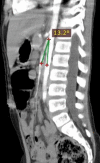

Background: Superior mesenteric artery syndrome (SMAS), also known as Wilkie's syndrome, is a rare disease that mainly presents as intestinal obstruction with a variable incidence ranging from 0.013 to 0.3% (Salehzadeh et al. in Case Rep Gastrointest Med, 2019, 10.1155/2019/3458601). In this syndrome, the third part of the duodenum, located between the abdominal aorta and the superior mesenteric artery, is wholly or partially obstructed (Mosalli et al. in J Pediatr Surg 46:e29-31, 2011). Case presentation An 8-years-old Arabian male patient was admitted to the gastrointestinal department at the pediatric hospital in Damascus, Syria, with complaints of chronic abdominal pain and periodic vomiting since he was two years old. At the age of Seven, he was diagnosed with appendicitis, and after two months of persistent symptoms, he was diagnosed with an umbilical hernia. Finally, after a long time of suffering, he was diagnosed with SMAS and underwent a successful surgical operation. After 3 months of follow-up, he was in good health with no symptoms.